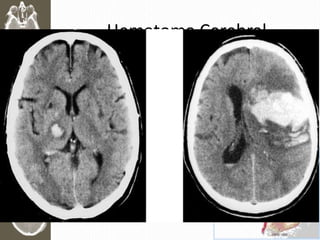

Hematoma Cerebral

• > 5ml intracerebral

• > frecuente Frontal y Temporal

• RAPIDO deterioro

• Mortalidad > 40%

Hematoma Epidural • Rupturade Art. Meníngea media • Parietooccipital: Desgarre Seno Venoso • Mortalidad 15 – 20%

• 39.

• El 50%con perdida transitoria de consciencia (periodo lucido 6 -18 hrs) • El 50% no recupera conciencia • Golpes en el hueso temporal (bate beisbol o vara billar) • Puede complicar en hernia en horas Biconvexidad Hiperdensa

• 40.

Hematoma Subdural • Tardamás en Formarse (Desgarro venoso) • Agudas: 24hrs (50-80% mortalidad) • Subaguda (25% mortalidad) • Crónica >2 semanas (20% mortalidad) Hematoma Crónico (Isodenso)

• 41.

Hematoma Cerebral • >5ml intracerebral • > frecuente Frontal y Temporal • RAPIDO deterioro • Mortalidad > 40%